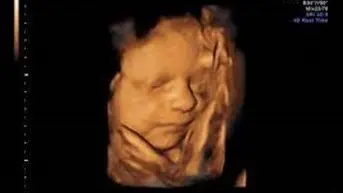

• ❤ Se realiza la evaluación estructural anatómica del feto de manera detallada, permite identificar que se hayan formado adecuadamente todos los órganos del bebé, permite detectar alteraciones o defectos estructurales.

• ❤ ¡Conocerás el sexo de tu bebé!

Todas las pacientes embarazadas deben realizarse este ultrasonido entre la semana 18-24 de gestación y solo deberá ser realizado por un médico especializado y altamente capacitado, como un médico materno fetal.